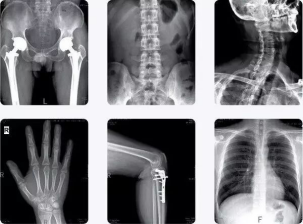

本学期,我校校医院坚持提高自身的医疗技术水平,以不断加强医院建设,积极更新陈旧设备,近日新添置了一套更为高精的DR(医用X线摄影系统)医疗设备。

数字化医用X射线摄影系统DR设备

数字化医用X射线摄影系统DR比传统X光成像具备更多优点:

我院引进的全新数字化X线摄影拍片系统,可为检查者提供从头至脚的X射线检查,表现为以下几大特点

第一 图像分辩率高覆盖更大

DR透射过人体后的X射线探测信号被关联的计算机获取,直接形成数字影像,图像层次更加丰富,图像清晰、细腻、对比度高。具备高级临床应用功能:ATH组织均衡(可为临床提供图像质量更高的影像,提高病变检出率),实现了人们梦寐以求的模拟X射线图像向数字化X射线图像的转变。

DR设备 通过大范围8方向悬浮床板达到便捷优秀的摆位,无论是颈、胸、腰、腿等常规体位还是特殊投照体位的拍摄,均可轻松完成。患者在检查过程中无需过多移动便可进行多种检查,方便我校离退休教职工,特别是高龄老人健康检查时的需要。

第二 X射线辐射降低

DR设备的数字化X线机形成的数字图像比传统胶片成像需要的X射线剂量减少,DR拍片的X剂量是传统CR拍照X剂量的1/10,用较低的X线剂量得到高清晰的图像,使病人减少了受X射线辐射的危害。

第三 成像速度快

新设备的使用使得患者全身照相更简便,图像更清晰,全长照相和以前的分段照相相比,出片时间缩短,曝光后10秒钟即可获得数字影像节省了患者的等候时间。

这套GMM数字化摄影系统为整机原装进口,GMM为意大利品牌,是欧洲最大的放射设备制造商之一,进入中国市场后以其良好的质量著称,是以欧洲最高人性化的设计要求来设计的悬吊式摄影系统。该品牌拍片时全部体位无死角覆盖、临床影像质量高、工作流程简化方便、长时间连续拍片状态稳定。